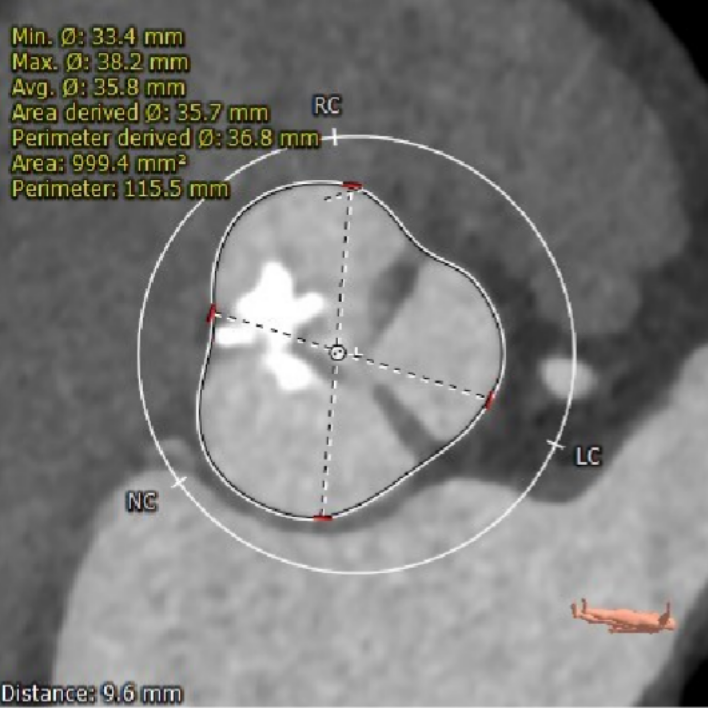

该患者为一例重度AS患者。Type1型二叶式主动脉瓣,瓣叶重度钙化并明显纤维增厚,右、无冠瓣融和成团块状钙化嵴,钙化灶分布不均匀,瓣口形状差,呈火山口状。假体瓣膜释放后有位移可能。

CT数据显示该患者为Type1主动脉瓣。

主动脉瓣瓣环周长80.8mm,平均周长径 25.7mm,SOV:34.8mm*34.3mm*33.4mm,瓣叶增厚,瓣上见右无钙化嵴,瓣环水平夹角42°。